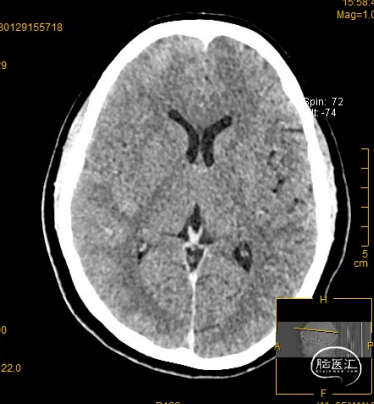

溶栓前颅脑CT提示考虑右侧大脑中动脉致密征,支持大脑中动脉为责任病变。

溶栓后颅脑CT见右侧大脑中动脉远端致密征,右外侧裂池变窄,同并见“岛带征”,考虑右侧急性脑梗塞,必要时进一步MR检查和/或CT脑灌注成像。